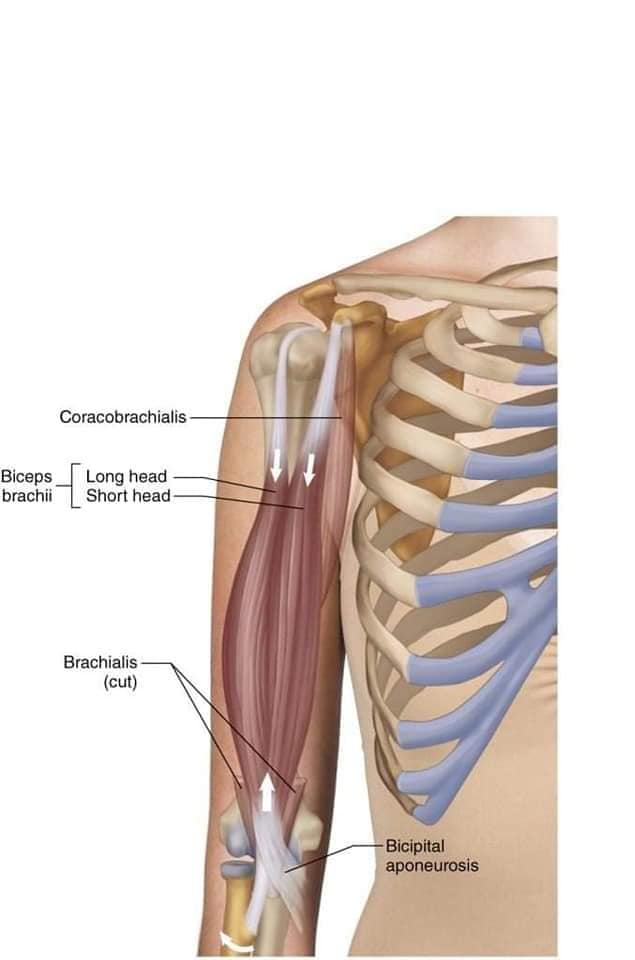

М'язова система людини є однією з основних систем організму, що відповідає за рухи, підтримання пози та стабільність. Вона складається з понад 600 м'язів, які можна класифікувати на скелетні, гладкі та серцеві м'язи. Скелетні м'язи, які є об'єктом нашого детального розгляду, дозволяють контролювати навколишній світ і виконувати різноманітні рухи. Особливу увагу в нашій статті буде приділено шейним і спинним м'язам, оскільки ці групи м'язів мають критичне значення для підтримання правильного постава та функціонування хребта.

Скелетні м'язи з'єднані з кістками за допомогою сухожиль і відповідають за більшість волевих рухів. Вони поділяються на:

- Швидкі м'язи - призначені для швидких і потужних рухів.

- Повільні м'язи - забезпечують стійкі і довготривалі рухи.

Скелетні м'язи мають поперечну смугасту структуру, що забезпечує їхню здатність до швидкого і ефективного скорочення.